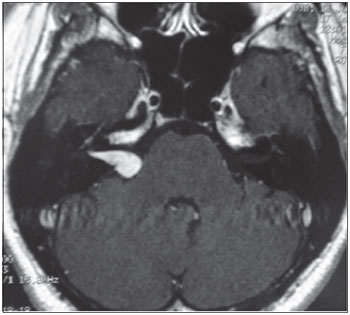

MRI was performed in 20 (95.2%) of 21 patients as 1 patient failed to complete the test. The MRI findings were normal in 16 (80%) patients and abnormal in 4 (20%). Analyzing the 4 abnormal tests, we found that in 2 cases the lesion arose from the eighth cranial nerve (schwannoma) ipsilateral to the SHL. In case 9, MRI revealed an expansive lesion inside the right IAC, protruding into the ipsilateral cerebellopontine angle (CPA) (Figure 5). In case 11, MRI showed an expansive lesion located in the right CPA and IAC, with enlargement and partial obliteration of the ipsilateral cistern (Figure 6). Among the 2 patients with eighth cranial nerve schwannomas, DPOAEs were absent in 1 (case 9) but present in the other (case 11). In this case, the test was performed later, during follow-up of SHL, and after complete recovery of audiometric hearing thresholds. Similarly, VEMP was absent in case 9 and present in case 11. ENG showed hypofunction in case 9 and no caloric function at all in case 11. In the other 2 cases with abnormal MRIs, the lesion was located in the cochlea on the same side as the SHL. The lesion was described by the radiologist as a focus of post-contrast enhancement in the cochlea, vestibule, and ipsilateral semicircular canals suggestive of inflammation (viral labyrinthitis, fibrotic tissue) in 1 (case 6), and as enhancement of the ipsilateral cochlea (possible inflammation) in the other (case 18). In the 2 latter cases, DPOAEs were absent, which was in agreement with the MRI findings showing cochlear enhancement, and helped to prove that the auditory lesion was peripheral, involving the OHCs, and not neural. VEMP was abnormal in case 6 and was not assessed in case 18. Thus, ENG showed no vestibular function ipsilateral to the lesion in both cases, even without any sign on MRI of a lesion extending into the posterior labyrinth in case 18.

Figure 5. Expansive lesion inside the right IAC.

Figure 6. Expansive lesion in the right IAC and CPA with widening and partial obliteration of the ipsilateral CPA cistern.